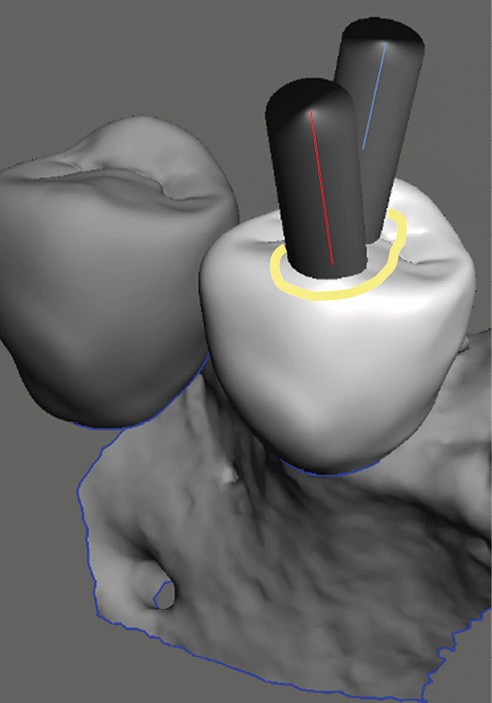

La cavité d’accès endodontique était alors traditionnellement réalisée en se figurant les axes de la racine et du bridge (fig. 2). Cette aptitude à s’orienter dans l’espace n’est cependant pas aisée, et différents outils numériques offrent aujourd’hui la possibilité de dessiner la trajectoire suspectée du canal sur les coupes de l’examen Cone Beam et d’aider le praticien à planifier son futur geste thérapeutique (fig. 3, 4). Après pose du champ opératoire, une voie d’accès est ainsi réalisée à travers le bridge en reportant les mesures de la planification 3D (fig. 5). Le tenon est déposé par vibration avec un insert ultrasonore puis la lecture des teintes dentinaires sous microscope permet d’objectiver la présence d’un canal supplémentaire non traité (fig. 6). Les surplombs dentinaires sont supprimés avec un insert ET18D (Actéon) et les entrées canalaires relocalisées avec une lime rotative d’évasement coronaire.